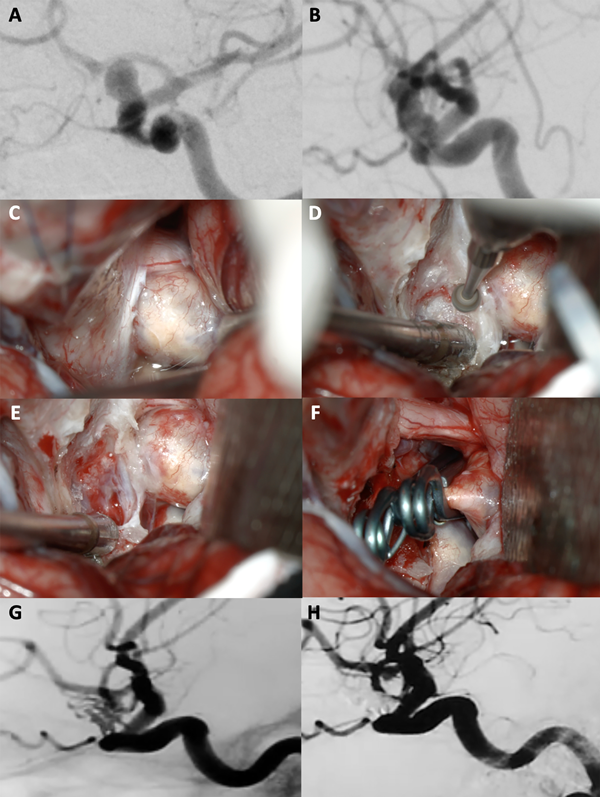

Figura 4. A-B: Se aprecia una arteriografía cerebral con reconstrucción tridimensional que evidencia un aneurisma carótido oftálmico izquierdo, nótese como la arteria oftálmica sale del domo del aneurisma. C-F: Fotografías intraoperatorias. Observamos la cisterna óptico-carotidea donde es visible el saco aneurismático ejerciendo gran efecto de masa sobre el nervio óptico. Posteriormente se realizó una clinoidectomía anterior parcial logrando una adecuada exposición del cuello del aneurisma. Se muestra la exclusión del aneurisma con un clip angulado. G-H: Imágenes de arteriografía cerebral post operatoria que evidencia la exclusión completa del aneurisma con preservación de la arteria oftálmica.